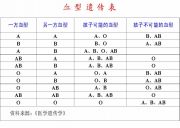

| 2021年7月26日 (一) 20:03 | 血型遗传规律.jpg (文件) |  |

77 KB | Uploaded with SimpleBatchUpload | 3 |